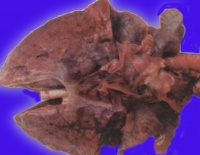

病理改变[编辑 | 编辑源代码]

肺表面苍白,含水量增多,切面有大量液体渗出显微镜下观察,可将其分为间质期,肺泡壁期和肺泡期。

间质期是肺水肿的最早表现,液体局限在肺泡外血管和传导气道周围的疏松结缔组织中,支气管、血管周围腔隙和叶间隔增宽,淋巴管扩张。液体进一步潴留时,进入肺泡壁期。液体蓄积在厚的肺泡毛细血管膜一侧,肺泡壁进行性增厚。发展到肺泡期时,可见充满液体的肺泡壁丧失了环形结构,出现褶皱。无论是微血管内压力增高还是通透性增加引起的肺水肿,肺泡腔内液体的蛋白均与肺间质内相同,提示表面活性物质破坏,而且上皮丧失了滤网能力。